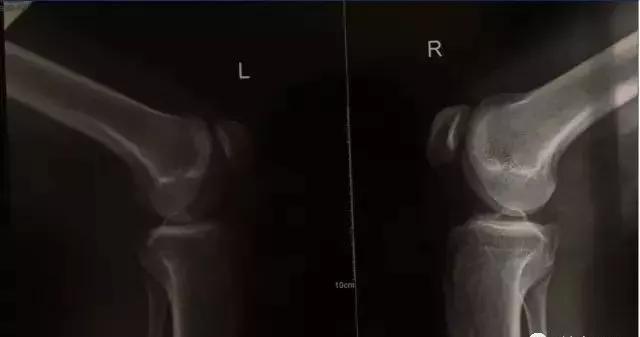

疼痛或者酸痛、冗长的弹响,多发于半月板,尤其是出现过半月板扭伤、磨损的人群,这种响声可能代表半月板的再次损伤。

病理性关节弹响是由于关节的损伤、疾病或结构的变异,致使滑膜粗糙,关节囊、韧带松弛,肌腱增生或腱鞘狭窄,关节盘破裂,关节软骨脱落等,在运动时就会因关节组织的摩擦产生弹响。

它可根据不同的病因和病理分为骨原性、滑膜原性、肌腱原性等多种,其响声可以是清脆的、沉闷的或磨砂样的,多数伴有疼痛或不适感,并且都是可以连续发生的。